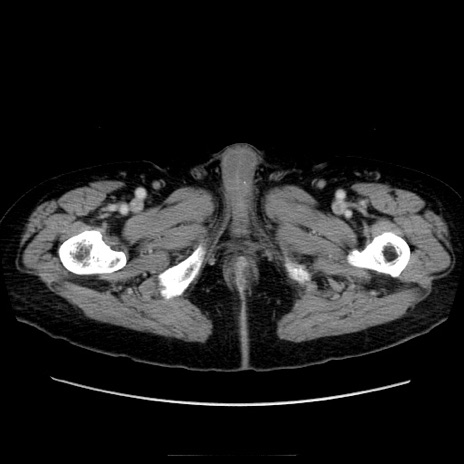

症例21(横断像)

【症例】70歳代男性

【主訴】腹痛

【現病歴】肝硬変・肝細胞癌にてかかりつけの方。約9時間前に食後より腹痛出現。症状が徐々に増悪し、嘔吐出現したため来院。

【既往歴】肝硬変、肝細胞癌(RFA、TACE後)

【身体所見】意識清明、表情苦悶様、BT 36℃、BP 129/78mmHg、P 88bpm、SpO2 97%(RA)、右上腹部から心窩部にかけて圧痛あり、反跳痛なし、筋性防御あり。

【データ】WBC 5800、CRP 0.16